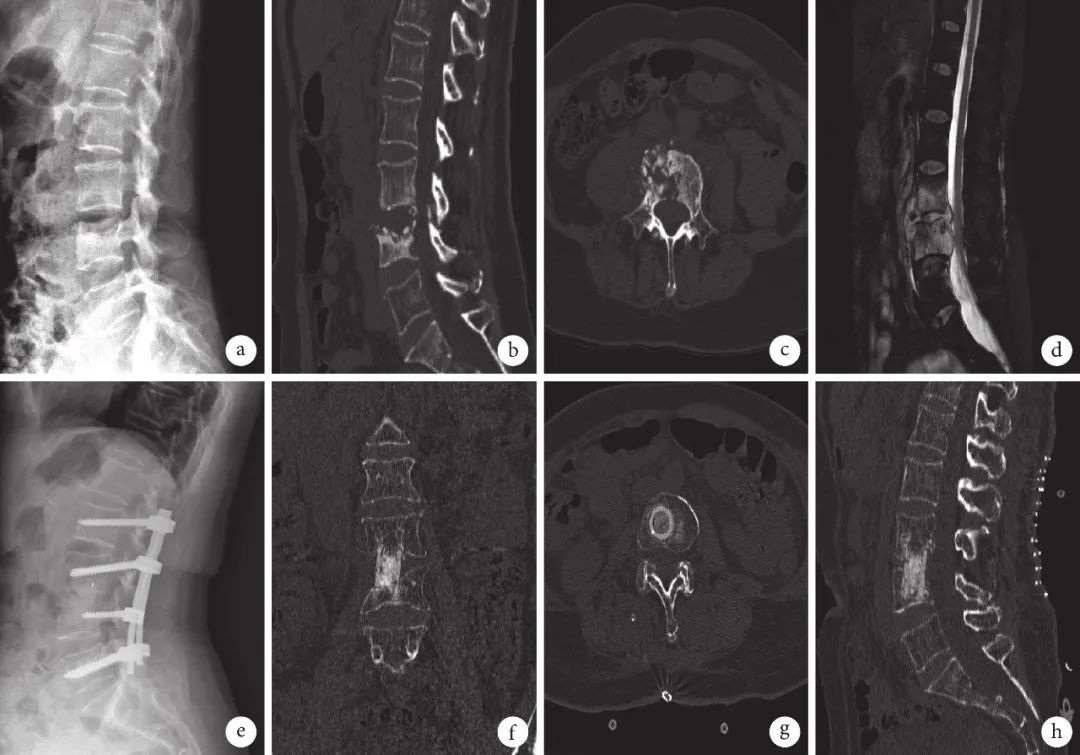

图 4 n-HA/PA66组患者,女,65岁,L3、4椎体结核 a. 术前X线片示椎体骨密度不均匀;b~d. 术前CT及MRI 示椎体多发骨质破坏,椎间隙变窄,椎旁脓肿形成压迫脊髓;e. 术后1 个月X线片示椎间融合及内固定物位置良好;f~h. 术后6个月CT示椎间植骨材料达骨性融合,椎间隙高度恢复